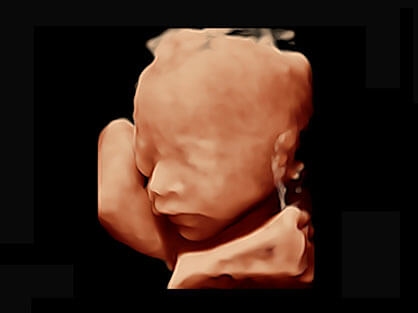

自动获取标准切面,自动完成测量,帮助医生快速完成检查,同时提升测量准确性。

宽频带腹部凸阵探头和腹部容积探头、大角度腔内探头和腔内容积探头、独特的生殖专用曲柄探头,为妇产应用提供全面诊疗方案。

卵泡结构的自动识别和测量,可显示多组测量数据。

大角度腔内容积探头,可完整包络子宫及盆底结构,充分展示组织结构毗邻关系。